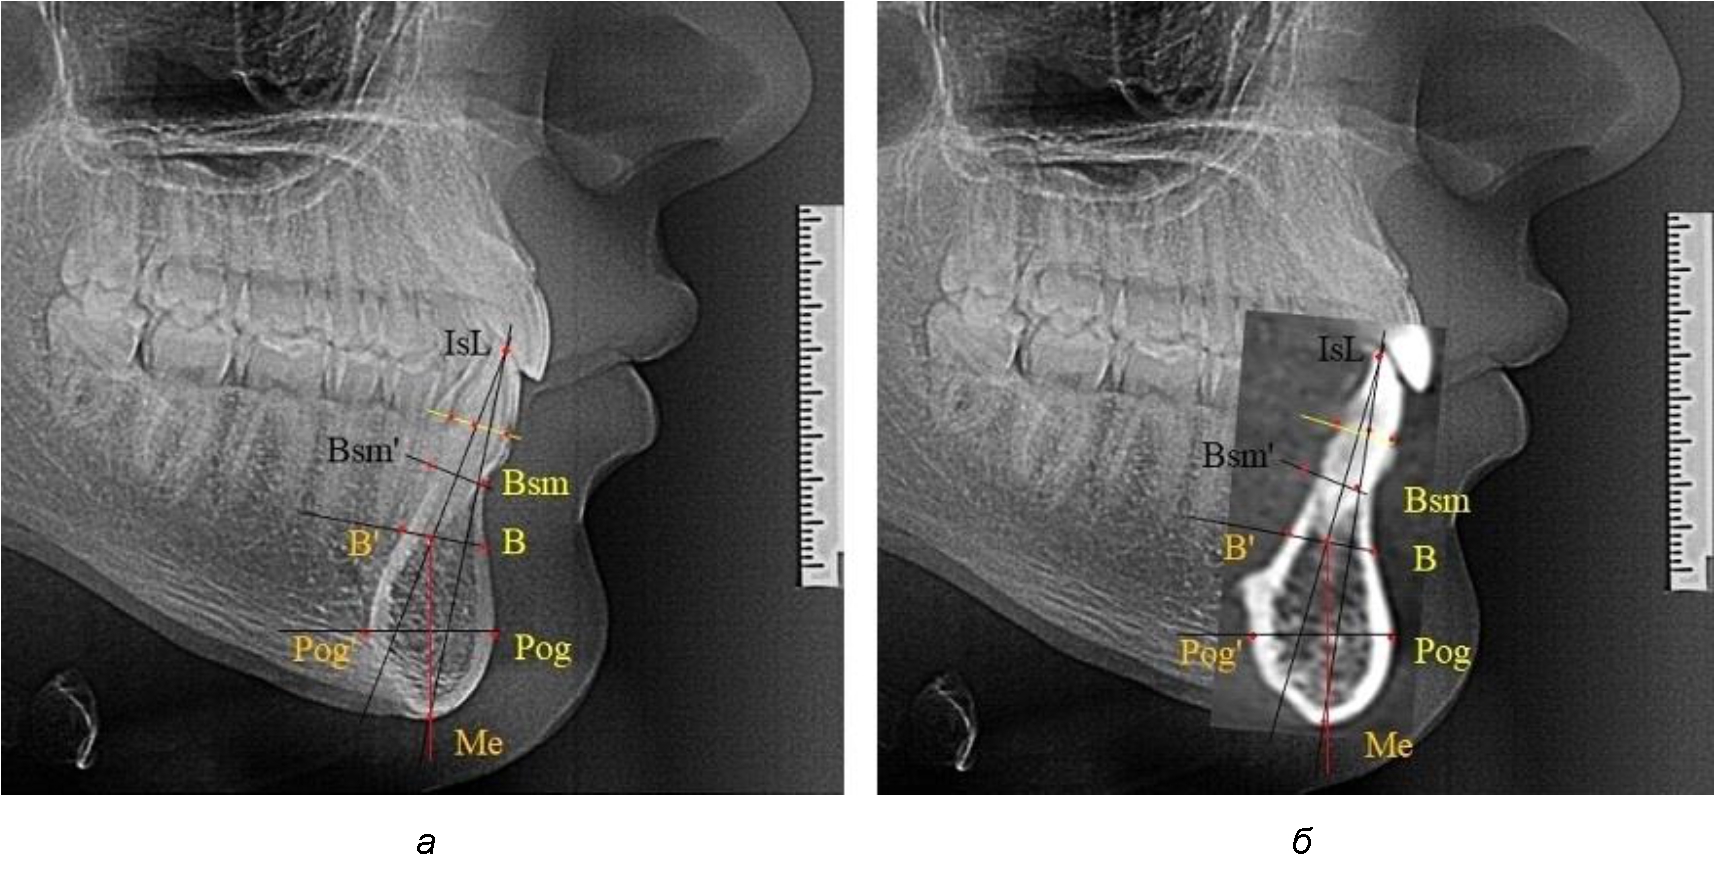

Типологические варианты подбородочного выступа, различающиеся по ширине, высоте и расположению апикальных точек, необходимо учитывать в клинике ортодонтии при проведении диагностических мероприятий. Протокольные точки для построения эстетических линий, исходящие из выступающей точки подбородка (Рog – погонион), не всегда могут быть объективным критерием диагностики, что объясняется различной выпуклостью переднего отдела подбородочного выступа. Точки апикального базиса по Шварцу и Даунсу находятся в различных местах подбородка и не всегда совпадают, что требует пояснения при выборе ориентиров. Кроме того, вариабельность сагиттальных размеров зубоальвеолярной части резцового сегмента позволит опти-мизировать методы перемещения резцов в переднее-заднем направлении и определяют костный биотип альвеолярной части нижней челюсти в анализируемой области.

При аномалиях окклюзии в сагиттальном направлении и характерных для них различных вариантах протрузионного и/или ретрузионного патологического положения передних зубов, как правило, сопровождается изменениями параметров подбородочного выступа. Учитывая многообразие форм аномалий окклюзии, параметры подбородочного выступа вариабельны как по сагиттали, так и по трансверсали.

Нередко отмечается деформация подбородочного выступа и различное его положение по отношению к зубоальвеолярной части сегмента. При мезиальной окклюзии нередко нижняя подбородочная точка смещается кзади по отношению к условной срединной вертикали нижнего резца, а при дистальной окклюзии отмечается компенсаторное отклонение подбородка кпереди (рис. 5).

Рис. 5. Особенности нижнечелюстного резцового сегмента на ТРГ у людей при мезиальной (а) и дистальной (б) окклюзии

Кроме того, так же как и у людей с физиологической окклюзией, определялось различие в положении апикальных точек Downs и Schwarz, что, по нашему мнению, может определять тактику лечения патологических форм протрузии/ретрузии резцов с учетом биотипа костной ткани.